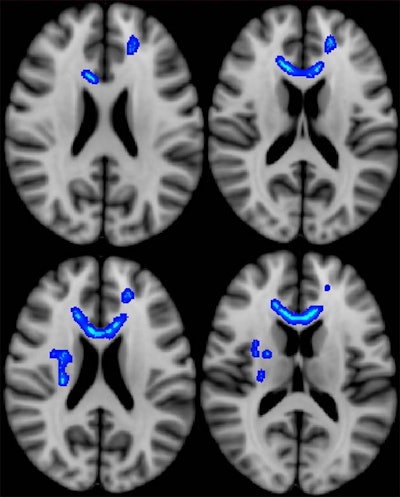

The researchers used DTI-MRI to detect abnormalities in the brain, particularly in the white matter, via measurements of water movement. They compared the results to clinical measures and patient outcomes six months to 2.5 years after the initial evaluation.

Ware and colleagues found significant associations between initial postdeployment DTI measurements and neurobehavioral symptoms, timing of injury, and subsequent functional outcomes. The measurements also correlated with greater use of healthcare services among veterans with mild TBI. All conventional MR images were interpreted as normal.

Following initial postdeployment evaluation, 34 study participants (60%) returned to work. Veterans who did not return to work displayed significantly lower fractional anisotropy and higher diffusivity, which suggest less structural integrity, in the left internal capsule, which is associated with motor stimulation to the typically dominant right side of the body.